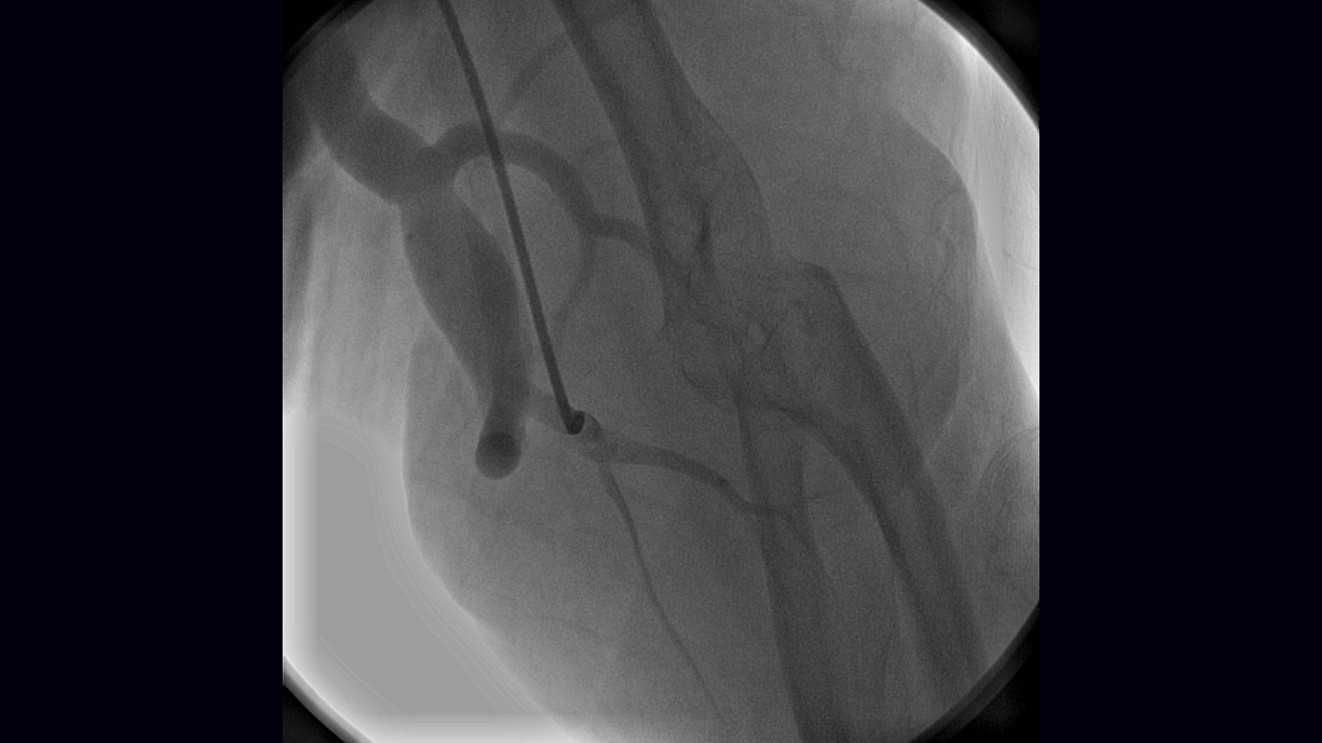

Embolisation Coils Fistula . Possible therapeutic options include surgical correction and transcatheter embolization. We describe a case of symptomatic coronary fistula treated with percutaneous coil. Stainless steel or platinum coils are commonly used in transcatheter closure of cafs, as they will. Transcatheter closure of caf with coronary coil is proven feasible and safe in the anatomically suitable vessel. Healthcare providers use endovascular coiling to block blood flow into an aneurysm. Transcatheter embolization techniques using coils (as is shown in the image below), bags, or other devices can be performed on an outpatient basis at the time of diagnostic. This procedure is also called endovascular embolization.

Transcatheter closure of caf with coronary coil is proven feasible and safe in the anatomically suitable vessel. Transcatheter embolization techniques using coils (as is shown in the image below), bags, or other devices can be performed on an outpatient basis at the time of diagnostic. Healthcare providers use endovascular coiling to block blood flow into an aneurysm. This procedure is also called endovascular embolization. Possible therapeutic options include surgical correction and transcatheter embolization. Stainless steel or platinum coils are commonly used in transcatheter closure of cafs, as they will. We describe a case of symptomatic coronary fistula treated with percutaneous coil.

RCASVC Fistula Before Coil Embolization Download Scientific Diagram Embolisation Coils Fistula We describe a case of symptomatic coronary fistula treated with percutaneous coil. Transcatheter closure of caf with coronary coil is proven feasible and safe in the anatomically suitable vessel. Stainless steel or platinum coils are commonly used in transcatheter closure of cafs, as they will. Healthcare providers use endovascular coiling to block blood flow into an aneurysm. Transcatheter embolization techniques. Embolisation Coils Fistula.